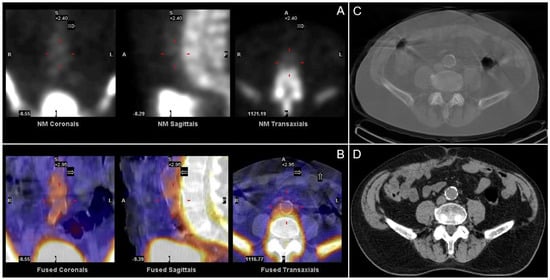

| 136 | Retrospective | 18F NaF uptake differentiated healthy controls from atherosclerotic patients, but CT-CAC could not. | [26] |

| 119 | Prospective | 18F NaF activity was higher in patients with atherosclerosis (p = 0.003), higher rates of previous cardiac events (p = 0.016), angina (p = 0.023), and correlated with CT-CAC (r = 0.652). | [18] |

| 32 | Retrospective | 18F NaF accumulation in coronary arteries correlates with a history of MI and CT-CAC. | [32] |